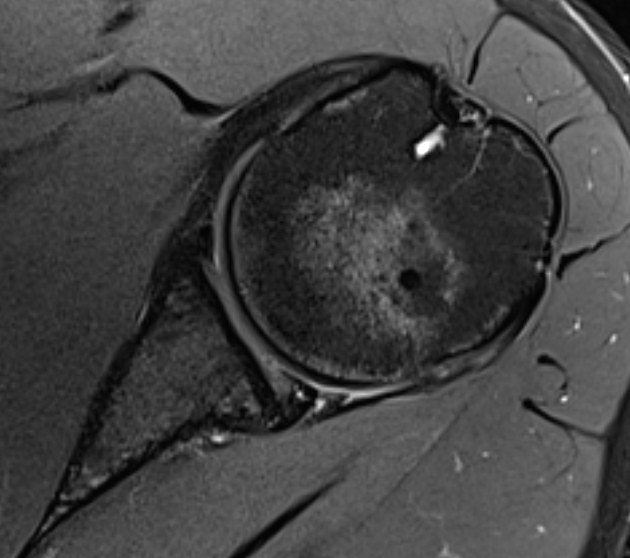

Posterior labral tear